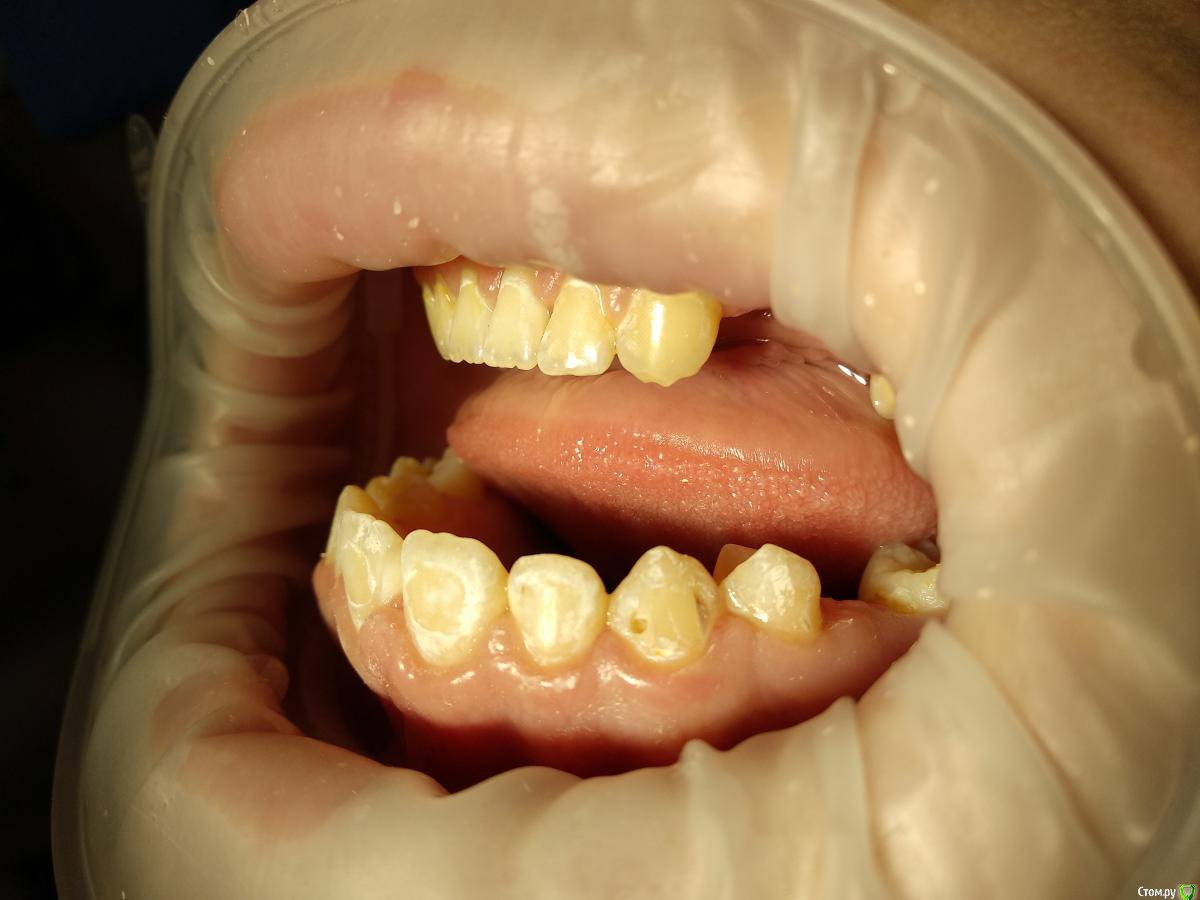

Paganini Опубликовано 13 октября, 2018 Поделиться Опубликовано 13 октября, 2018 (изменено) Приветствую! Помогите помочь пациенту (13 лет). Попросила ортодонта снять брекеты досрочно, потому что с эмалью беда - эмаль скалывается кусками, в местах под брекетами множественные дефекты. При нажатии на эмаль зондом остаются следы. Уверена, что до установки брекетов была уже патология (флюороз или гипоплазия), брекеты всего лишь усугубили ситуацию. С гигиеной тоже все плохо: всегда, когда пациент приходил ко мне на чистку, налета столько, что хоть ложкой снимай... Ставить пломбы? Дефектов очень много, и я думаю, что держаться это будет плохо, эмаль хрупкая. Сейчас комплексно укрепляем эмаль.P.S.: я не детский врач. Я гигиенист и терапевт с небольшим опытом работы. Изменено 13 октября, 2018 пользователем Paganini Ссылка на комментарий

Paganini Опубликовано 13 октября, 2018 Автор Поделиться Опубликовано 13 октября, 2018 Пострадали почти все резцы и клыки, жевательная группа в порядке, но там мало что есть (первичная адентия). Ссылка на комментарий

St. Опубликовано 14 октября, 2018 Поделиться Опубликовано 14 октября, 2018 1. учить чистить, мотивировать и контролировать домашнюю гигиену, без этого толку не будет. если необходимо чаще вызывать на проф.гигиену2. пломбировка где уже есть дефекты эмали.3. рем терапия или возможно айкон где только пятна без дефекта. 1 Ссылка на комментарий